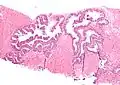

Néoplasie prostatique intraéphithéliale de haut grade (HGPIN)